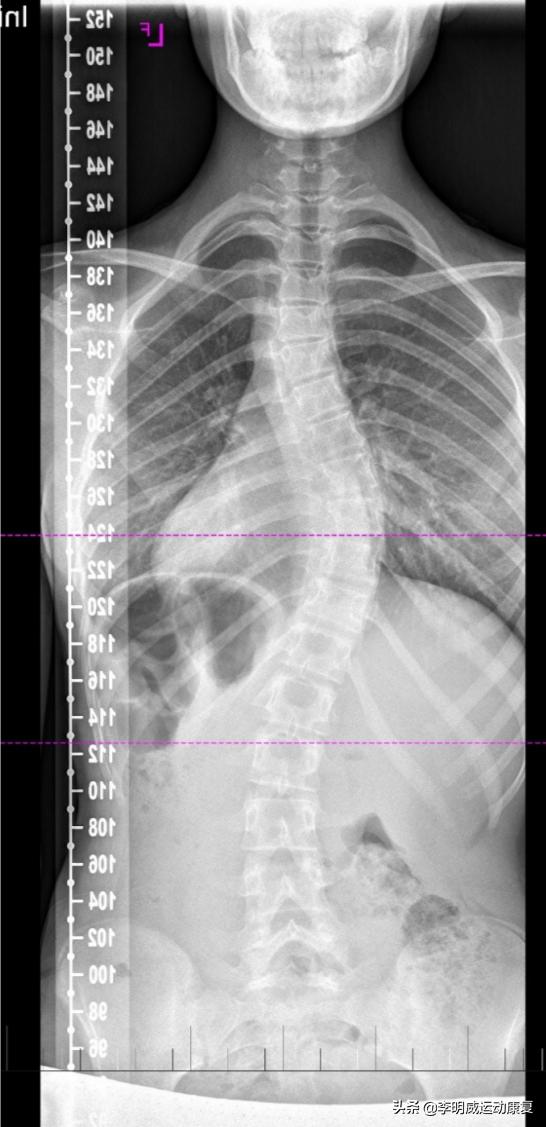

脊柱侧弯是脊柱发生的横向弯曲,最经常发生在青春期之前的快速增长期间。尽管脊柱侧弯可以由肌肉营养不良等疾病引起,但大多数脊柱侧弯的原因尚不清楚。大约5%的青少年患有脊柱侧弯。

脊柱侧弯的大多数病例为轻度,但随着儿童的成长,一些脊柱畸形继续变得更加严重。严重的脊柱侧弯可能会导致残疾。特别严重的脊柱弯曲会减少胸部的空间,使肺部难以正常运作。

X射线对患有轻度脊柱侧弯的儿童进行密切监视,以查看曲线是否在恶化。在许多情况下,无需治疗。一些孩子将需要系好安全带以防止曲线恶化。其他人可能需要手术以防止脊柱侧弯恶化,并纠正严重的脊柱侧弯病例。